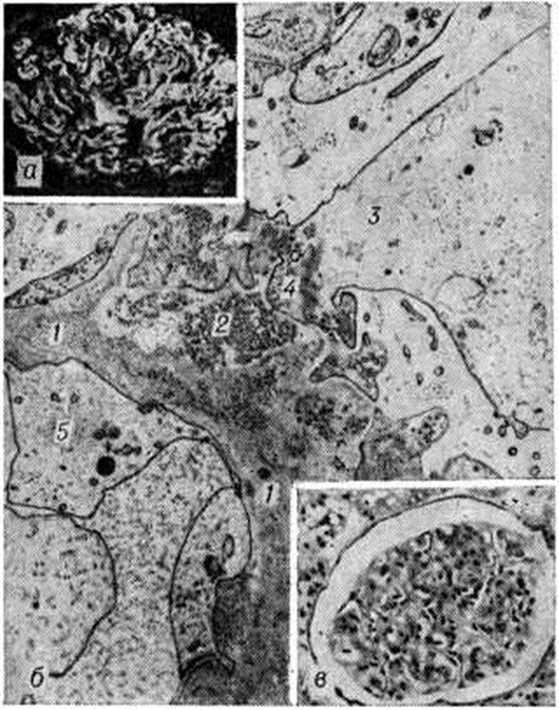

Рис. 4.

Микропрепарат (б) и электронограмма (а) почки при мембранозно-пролиферативном гломерулонефрите: а — пролиферация мезангиальных клеток (1), появление отростков этих клеток (2) вблизи депозитов (3) иммунных комплексов в базальной мембране (4); расширение мезангия (5); ворсинчатая трансформация подоцитов (б); ×20 000; б — гистологическая картина мембранозно-пролиферативного гломерулонефрита (окраска гематоксилинэозином); ×200.

Мембранозно-пролиферативный Гломерулонефрит, хронический латентный или подострый нефрит, гипокомплементарный персистирующий, хронический лобулярный, смешанный, мезангиокапиллярный Гломерулонефрит — одна и та же форма, для которой морфологически характерны пролиферация мезангиоцитов и утолщение стенок капилляров клубочка [Камерон (J. S. Cameron) и соавторами, 1970], а клинически — хронический течение, протеинурия, реже гематурия и в ряде случаев отсутствие эффекта при лечении стероидными гормонами. Хотя за этим типом Гломерулонефрит и утвердился термин «мембранозно-пролиферативный», правильнее называть его мезангиопролиферативным [Мандаленакис (N. N. MandaJenakis) и соавторами, 1971], так как гломерулярные изменения при нем, в том числе и мембранозные, связаны прежде всего с пролиферацией мезангиальных клеток и интерпозицией мезангия. С помощью электронной микроскопии (рисунок 4 а) определяется резкое расширение мезангия за счёт пролиферации его клеток и увеличения матрикса. Расширение мезангия ведёт к его интерпозиции [Аракава и Киммелстил (М. Arakawa, P. Kimmelstiel), 1969] — отростки мезангиоцитов, окружённые мембраноподобным веществом, выходят за пределы соединительной ткани клубочка и, распространяясь вдоль базальной мембраны на периферию капиллярной петли, отодвигают эндотелий. При световой микроскопии выявляется феномен утолщения (рисунок 4,6) и расщепления мембраны. Пролиферация мезангиоцитов, наблюдаемая, как правило, вблизи депозитов иммунных комплексов, может быть ограничена эндотелиальной выстилкой (при этом просвет капилляра сохраняется свободным), либо пролиферирующие клетки прорывают эндотелиальную выстилку и заполняют частично или полностью просвет капилляра. Повышенная секреция пролиферирующими мезангиоцитами тропоколлагена ведёт к накоплению мембраноподобного вещества в стенке и просвете капилляров, что лежит в основе склероза и гиалиноза клубочков. Сужению просвета капилляров способствует также пролиферация эндотелия, однако она значительно уступает пролиферации мезангиальных клеток Изменения подоцитов разнообразны от гиперплазии ультраструктур, отражающей повышенную функциональную нагрузку, до глубокой дистрофии в виде редукции малых отростков, вакуолизации цитоплазмы, ворсинчатой трансформации клеток.